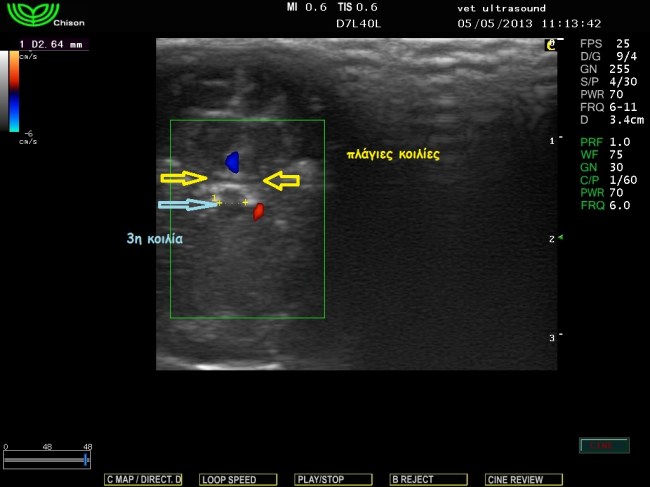

Στην κλινική εξέταση δεν παρατηρήθηκαν αλλοιώσεις στην νευρολογική εξέταση των εγκεφαλικών συζυγιών και των νωτιαίων νεύρων. Υπήρχε μία μικρή απόκλιση των οφθαλμών από τον κεντρικό άξονα και για τον λόγο αυτό είχε θορυβηθεί ο ιδιοκτήτης. Δεν είχε επέλθει οστεοποίηση των συναρθρώσεων των οστών του κρανίου, οπότε η υπερηχοτομογραφική εξέταση ήταν εφικτή διαμέσου της συνάρθρωσης των βρεγματικών με τα μετωπιαία οστά. Δεν υπήρχε διάταση των πλάγιων κοιλιών του εγκεφάλου και έτσι το ενδεχόμενο του υδροκέφαλου αποκλείστηκε.

εγκάρσια τομή τελείως κάθετη στον επιμήκη άξονα του κρανίου.